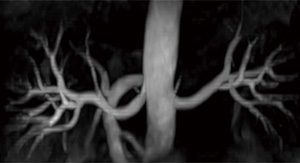

頭部での3D-T2強調撮像に使用されてきたsyngo SPACEは,腹部でもT2撮像に応用されている。可変フリップアングルを使用しT2減衰をコントロールするこの方法では,同じエコートレインのHASTEと比較して画像がシャープであることが知られている。

SPACEを使用することによって,3D-MRCPでもより辺縁のシャープな画像を得ることが可能である(図6)。

図6 3D-MRCP(syngo SPACE+ PACE)